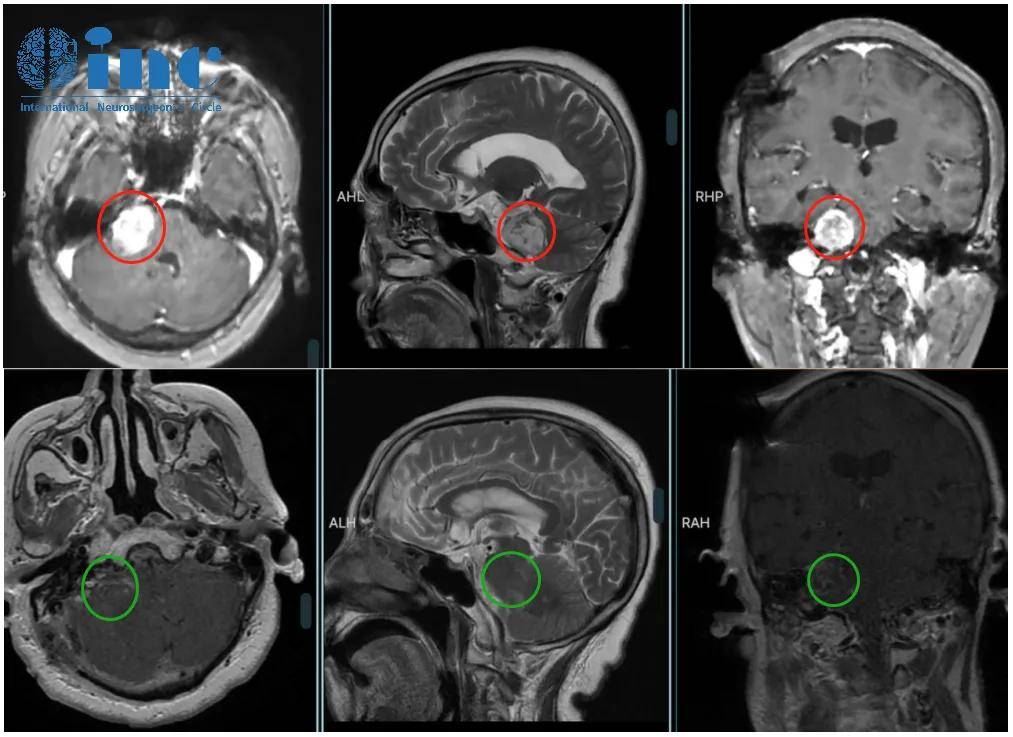

78岁高龄患者李奶奶(化名)确诊听神经瘤一年后,肿瘤迅速增长至超过3厘米,属于大型听神经瘤范畴。病情进展引发严重临床症状:听力显著下降、脑积水、步态不稳、下肢无力等表现,对生命健康构成严重威胁。

2022年巴特朗菲教授在华学术交流期间,亲自为李奶奶实施高难度听神经瘤显微切除术。手术成功实现肿瘤全切,神经功能保护良好。术后一年随访显示,患者康复状况良好,精神饱满,能与家人正常互动。